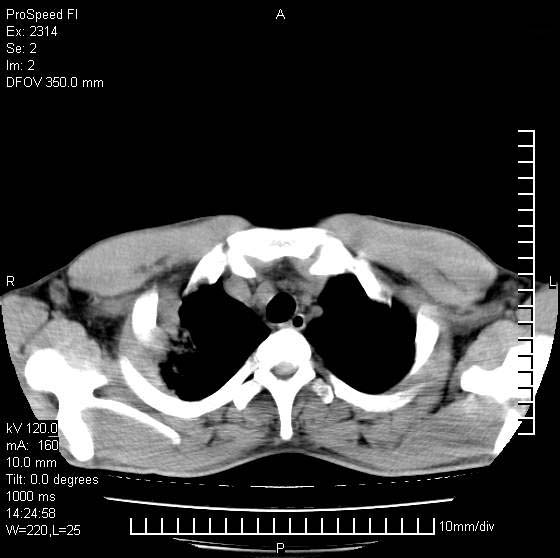

男性,再生障碍性贫血,入院前发热10天,最高40c,右侧胸痛,外院ct示右上,中肺边缘模糊的球性影(就是我现在图中标示的范围),考虑炎症,在我院使用头孢呋辛,洛美沙星10天,高烧消退,自感下午稍有发热,但今天ct示右上,中肺病灶明显扩大,还是考虑炎症,看其中的球型影是否霉菌感染??,是否能排除结核?